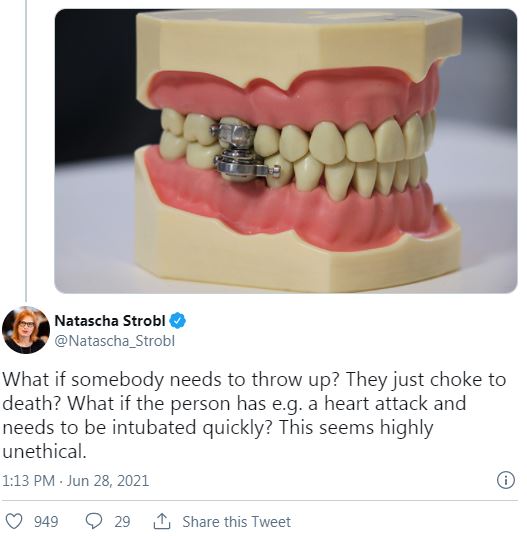

然而,有受試者在網路上分享,「齒科飲食控制裝置」讓他非常不舒服,而且很難講話,生活品質受到不小的影響。有受試者甚至「作弊」將巧克力融化和喝汽水違反節食規定。網友們對於這個裝置感到憂心,認為萬一佩戴者不舒服想吐,或是需要緊急做插管治療就會因為這個裝置發生危險,覺得這個裝置根本就是刑具。

圖片來源 / 翻攝自推特,下同

還有人認為根本沒有必要用這種極端的方法減重,這種強迫性的飲食方式非常不健康,而且一旦將裝置拆除恢復正常飲食,體重很快又恢復了,但對身體的傷害已經造成。